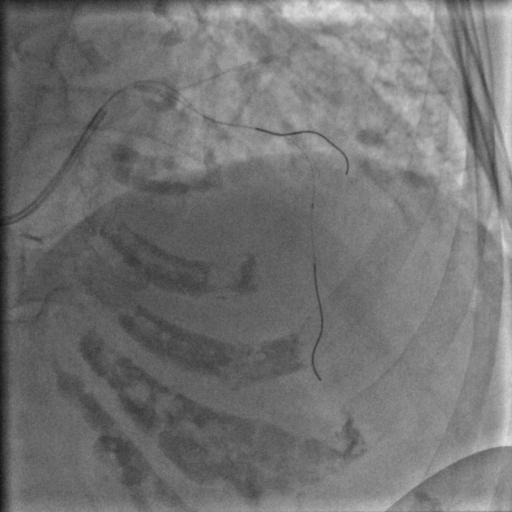

按照常规,更换指引导管,送入导丝,顺利通过闭塞病变到达前降支远端,很顺利,D-to-B时间70分钟,达标,曙光在前头。

图5

导丝过了之后常规造个影:

图6

没通,这个也很正常,急性冠脉闭塞导丝过了之后血栓还堵着是很经常的事,按常规打点欣维宁,考虑到她86岁,打入8ml欣维宁,造影: